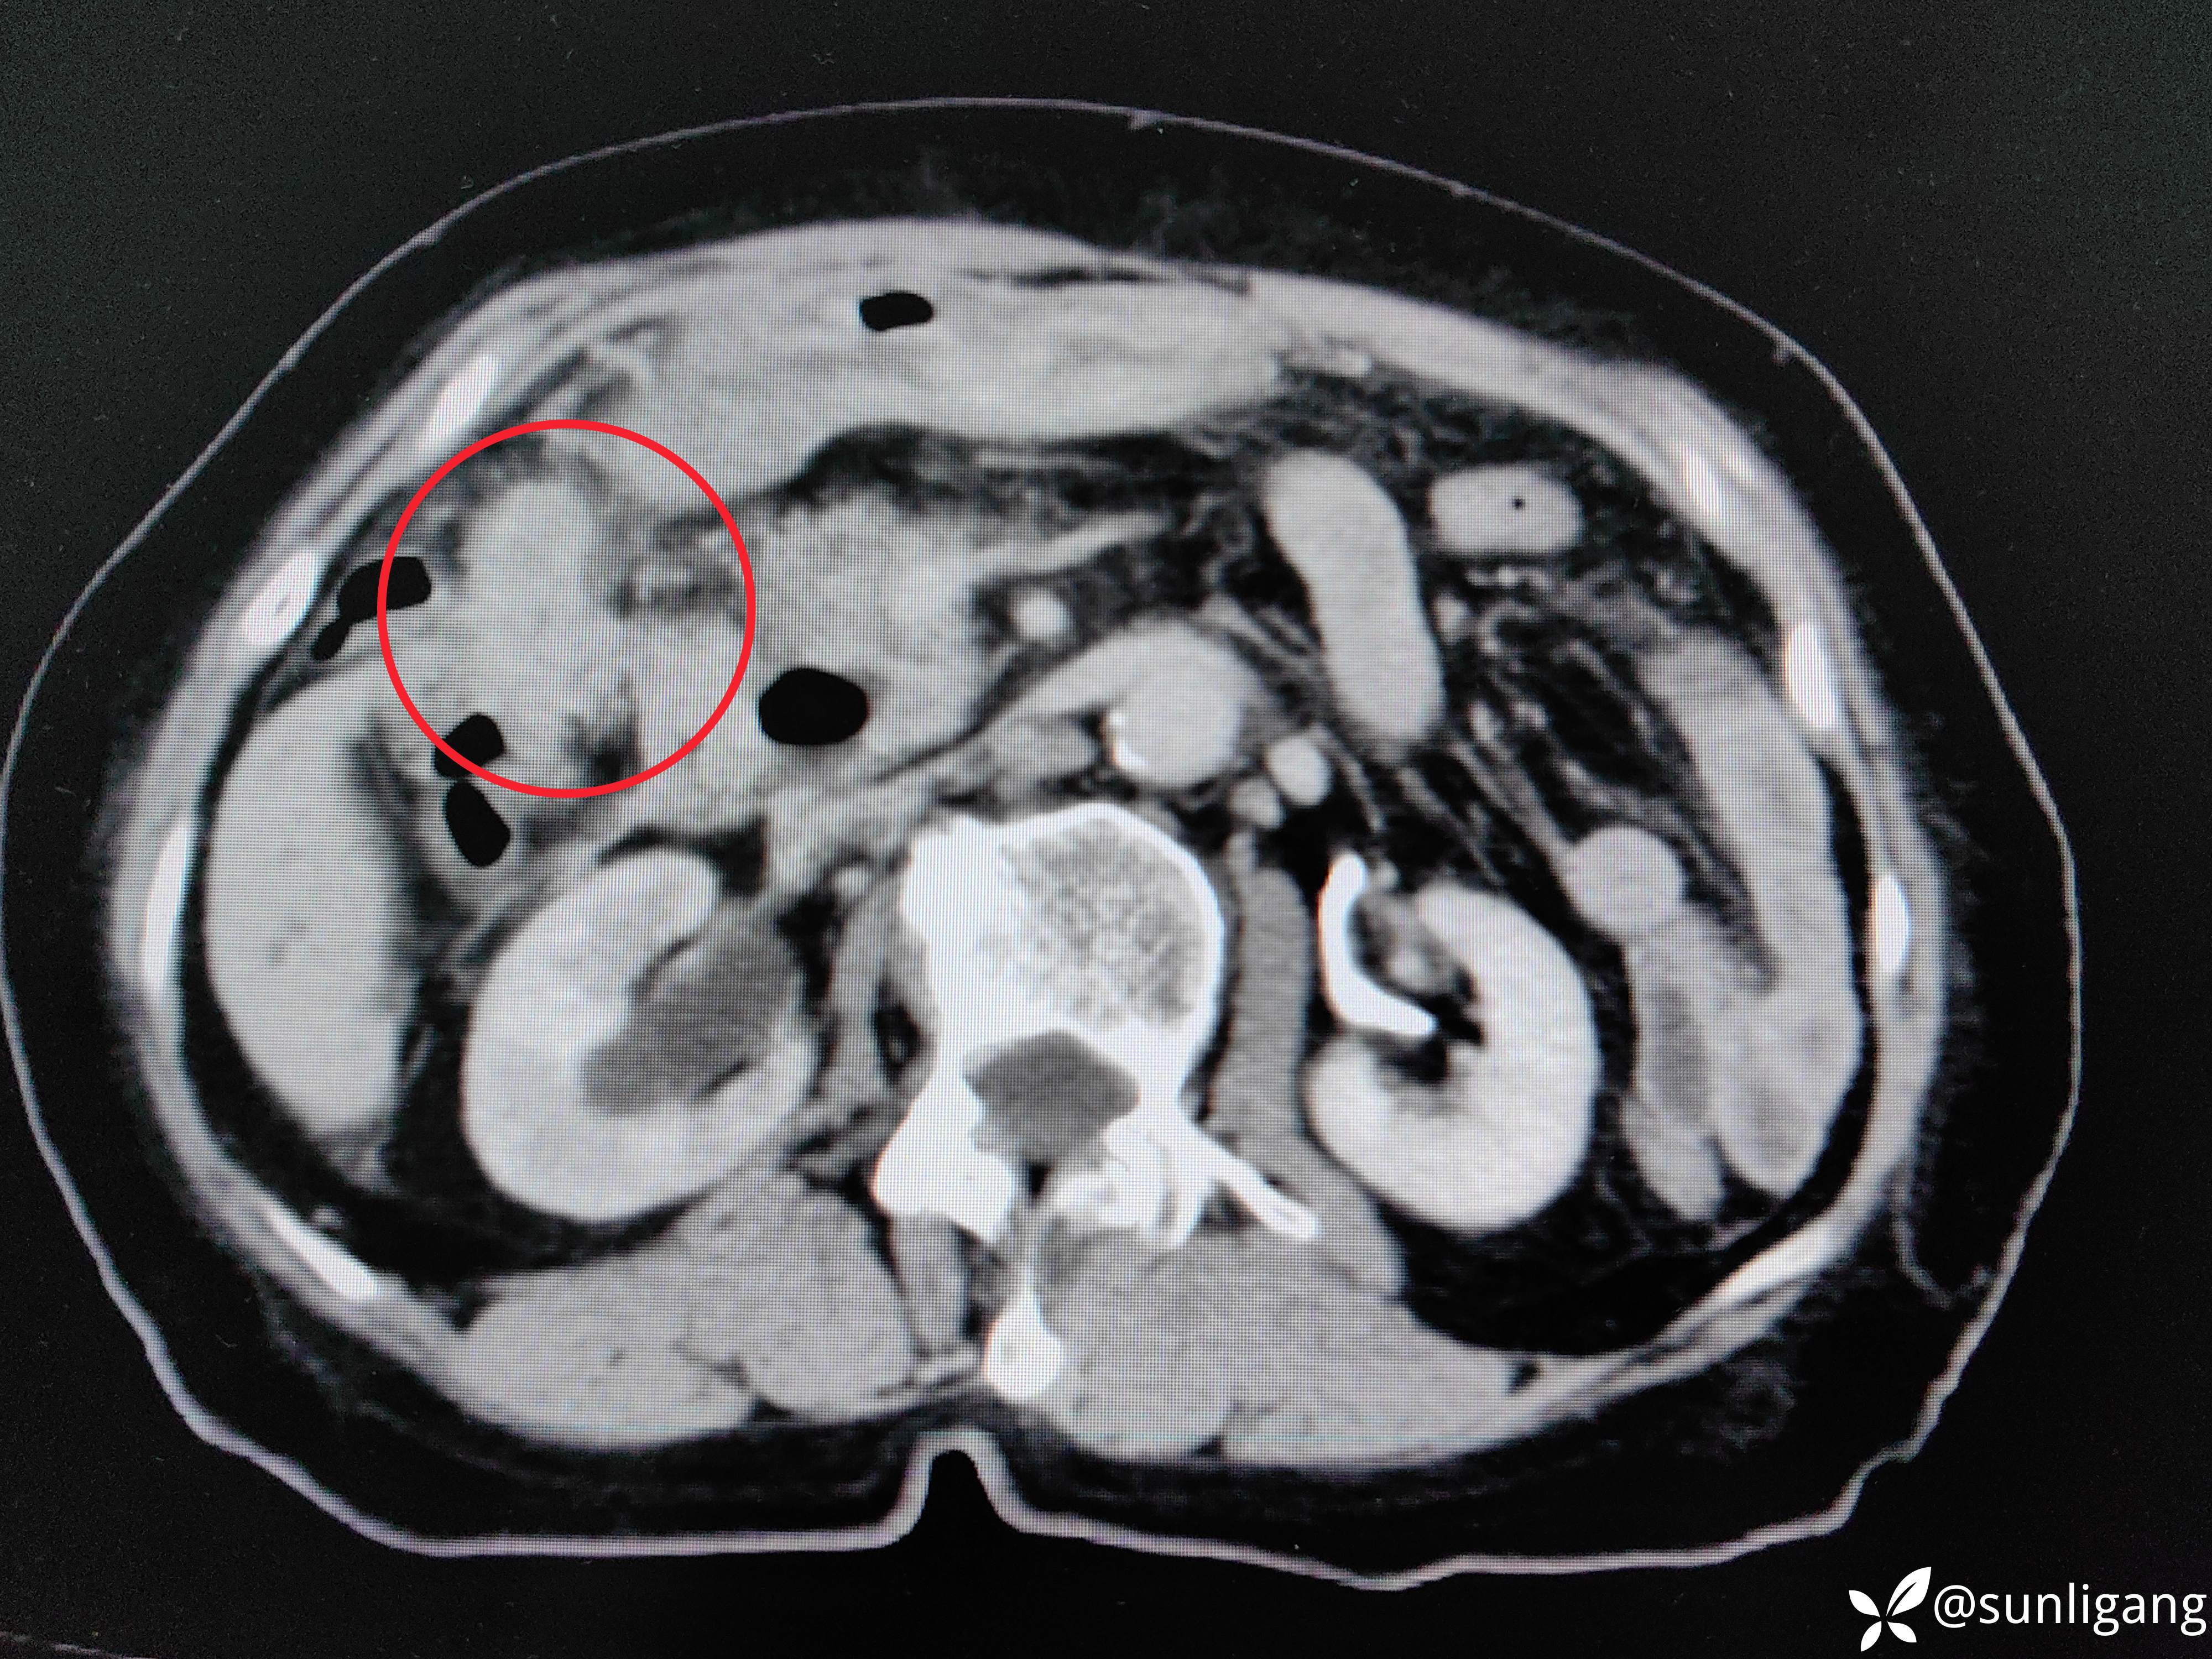

层面继续往下:

胆囊牵拉肝脏,使局部肝脏边缘内陷

胆囊与肝脏间已无明显界限,肝脏边缘内陷

增厚的胆囊壁

局部已无正常组织间隙,如肝与结肠、肝与胃之间,可见到明显的肿物,还有十二指肠憩室